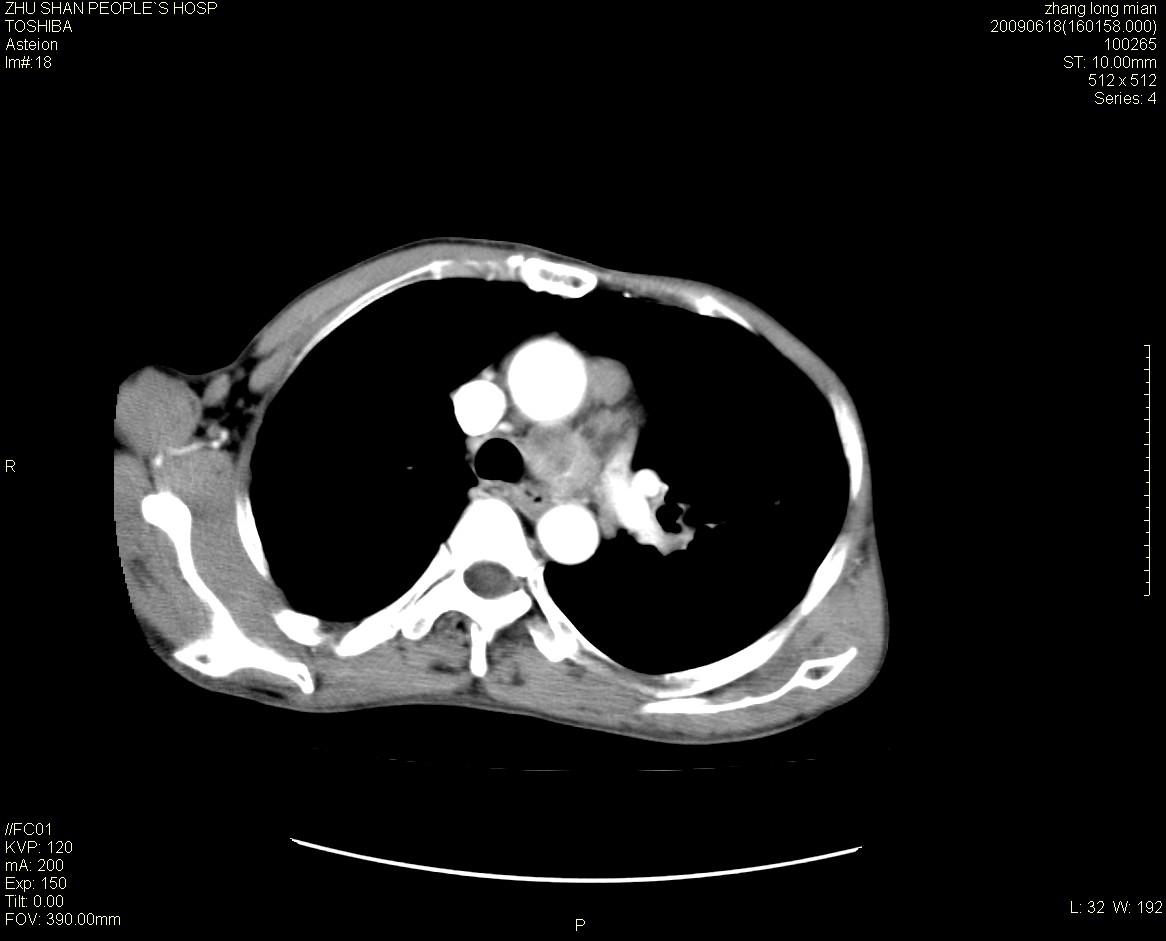

男性 65岁 胸片发现右下肺包块.诊断肺ca并纵隔转移没有问题吧!

两侧胸廓不对称,右侧呈塌陷改变,右肺萎缩。

右下肺见浅分叶状软组织块影,边缘有毛刺,其下部似见不完整偏心空洞影,邻近胸膜凹陷征,并胸腔积液。

增强见纵隔区气管隆突上下及左肺门区肿大淋巴结。左肺感染性病灶。

另见右上肺见一枚小结节影,性质待定。